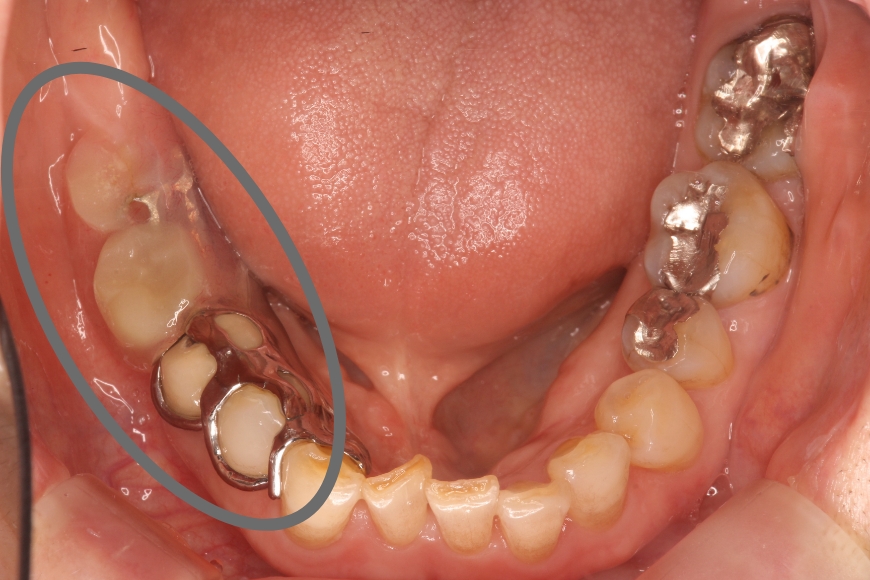

50代男性 左下の奥歯へのインプラント治療

治療内容 左下の奥歯が無く、食事がうまくできないことを主訴に来院されました。

歯が無い箇所にインプラント治療を行うことで、奥歯でしっかりと噛めるようになり、食事がおいしくなったとのことです。

治療期間・回数 治療期間:約3ヶ月

通院回数:5回程度

治療費用(総額)

440,000